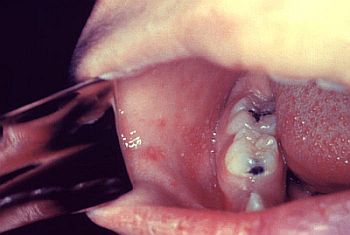

Κηλίδες KoplikΚηλίδες Koplik Η ιλαρά αρχίζει με μια πρόδρομη αναπνευστική φάση 2-4 ημερών που εμφανίζεται με αίσθημα κακουχίας, βήχα, κόρυζα, επιπεφυκίτιδα με δα­κρύρροια, ρινικό καταρροή και αυξανόμενο πυρετό (με θερμοκρασίες έως 40,6°C). Στο στάδιο αυτό της νόσου, κατά το οποίο το εξάνθημα ακόμη δεν έχει εμφανιστεί, είναι πιθανόν να δημιουργηθεί σύγχυση με τη γρίπη. Λίγο πριν την έναρξη του εξανθήματος εμφανίζονται οι κηλίδες Koplik ως κυανόλευκες κηλίδες 1-2 mm επί έντονα ερυθρής βάσης που εντοπίζονται χαρακτηριστικά στον στοματικό βλεννογόνο, παραπλεύρως των δεύτερων γομφίων και υποχωρούν μετά την έναρξη του εξανθήματος και σύντομα εξαφανίζονται (ουσιαστικά πρόκειται για ανοσοαπαντήσεις κατά του ιού στα ενδοθηλιακά κύτταρα των τριχοειδών).